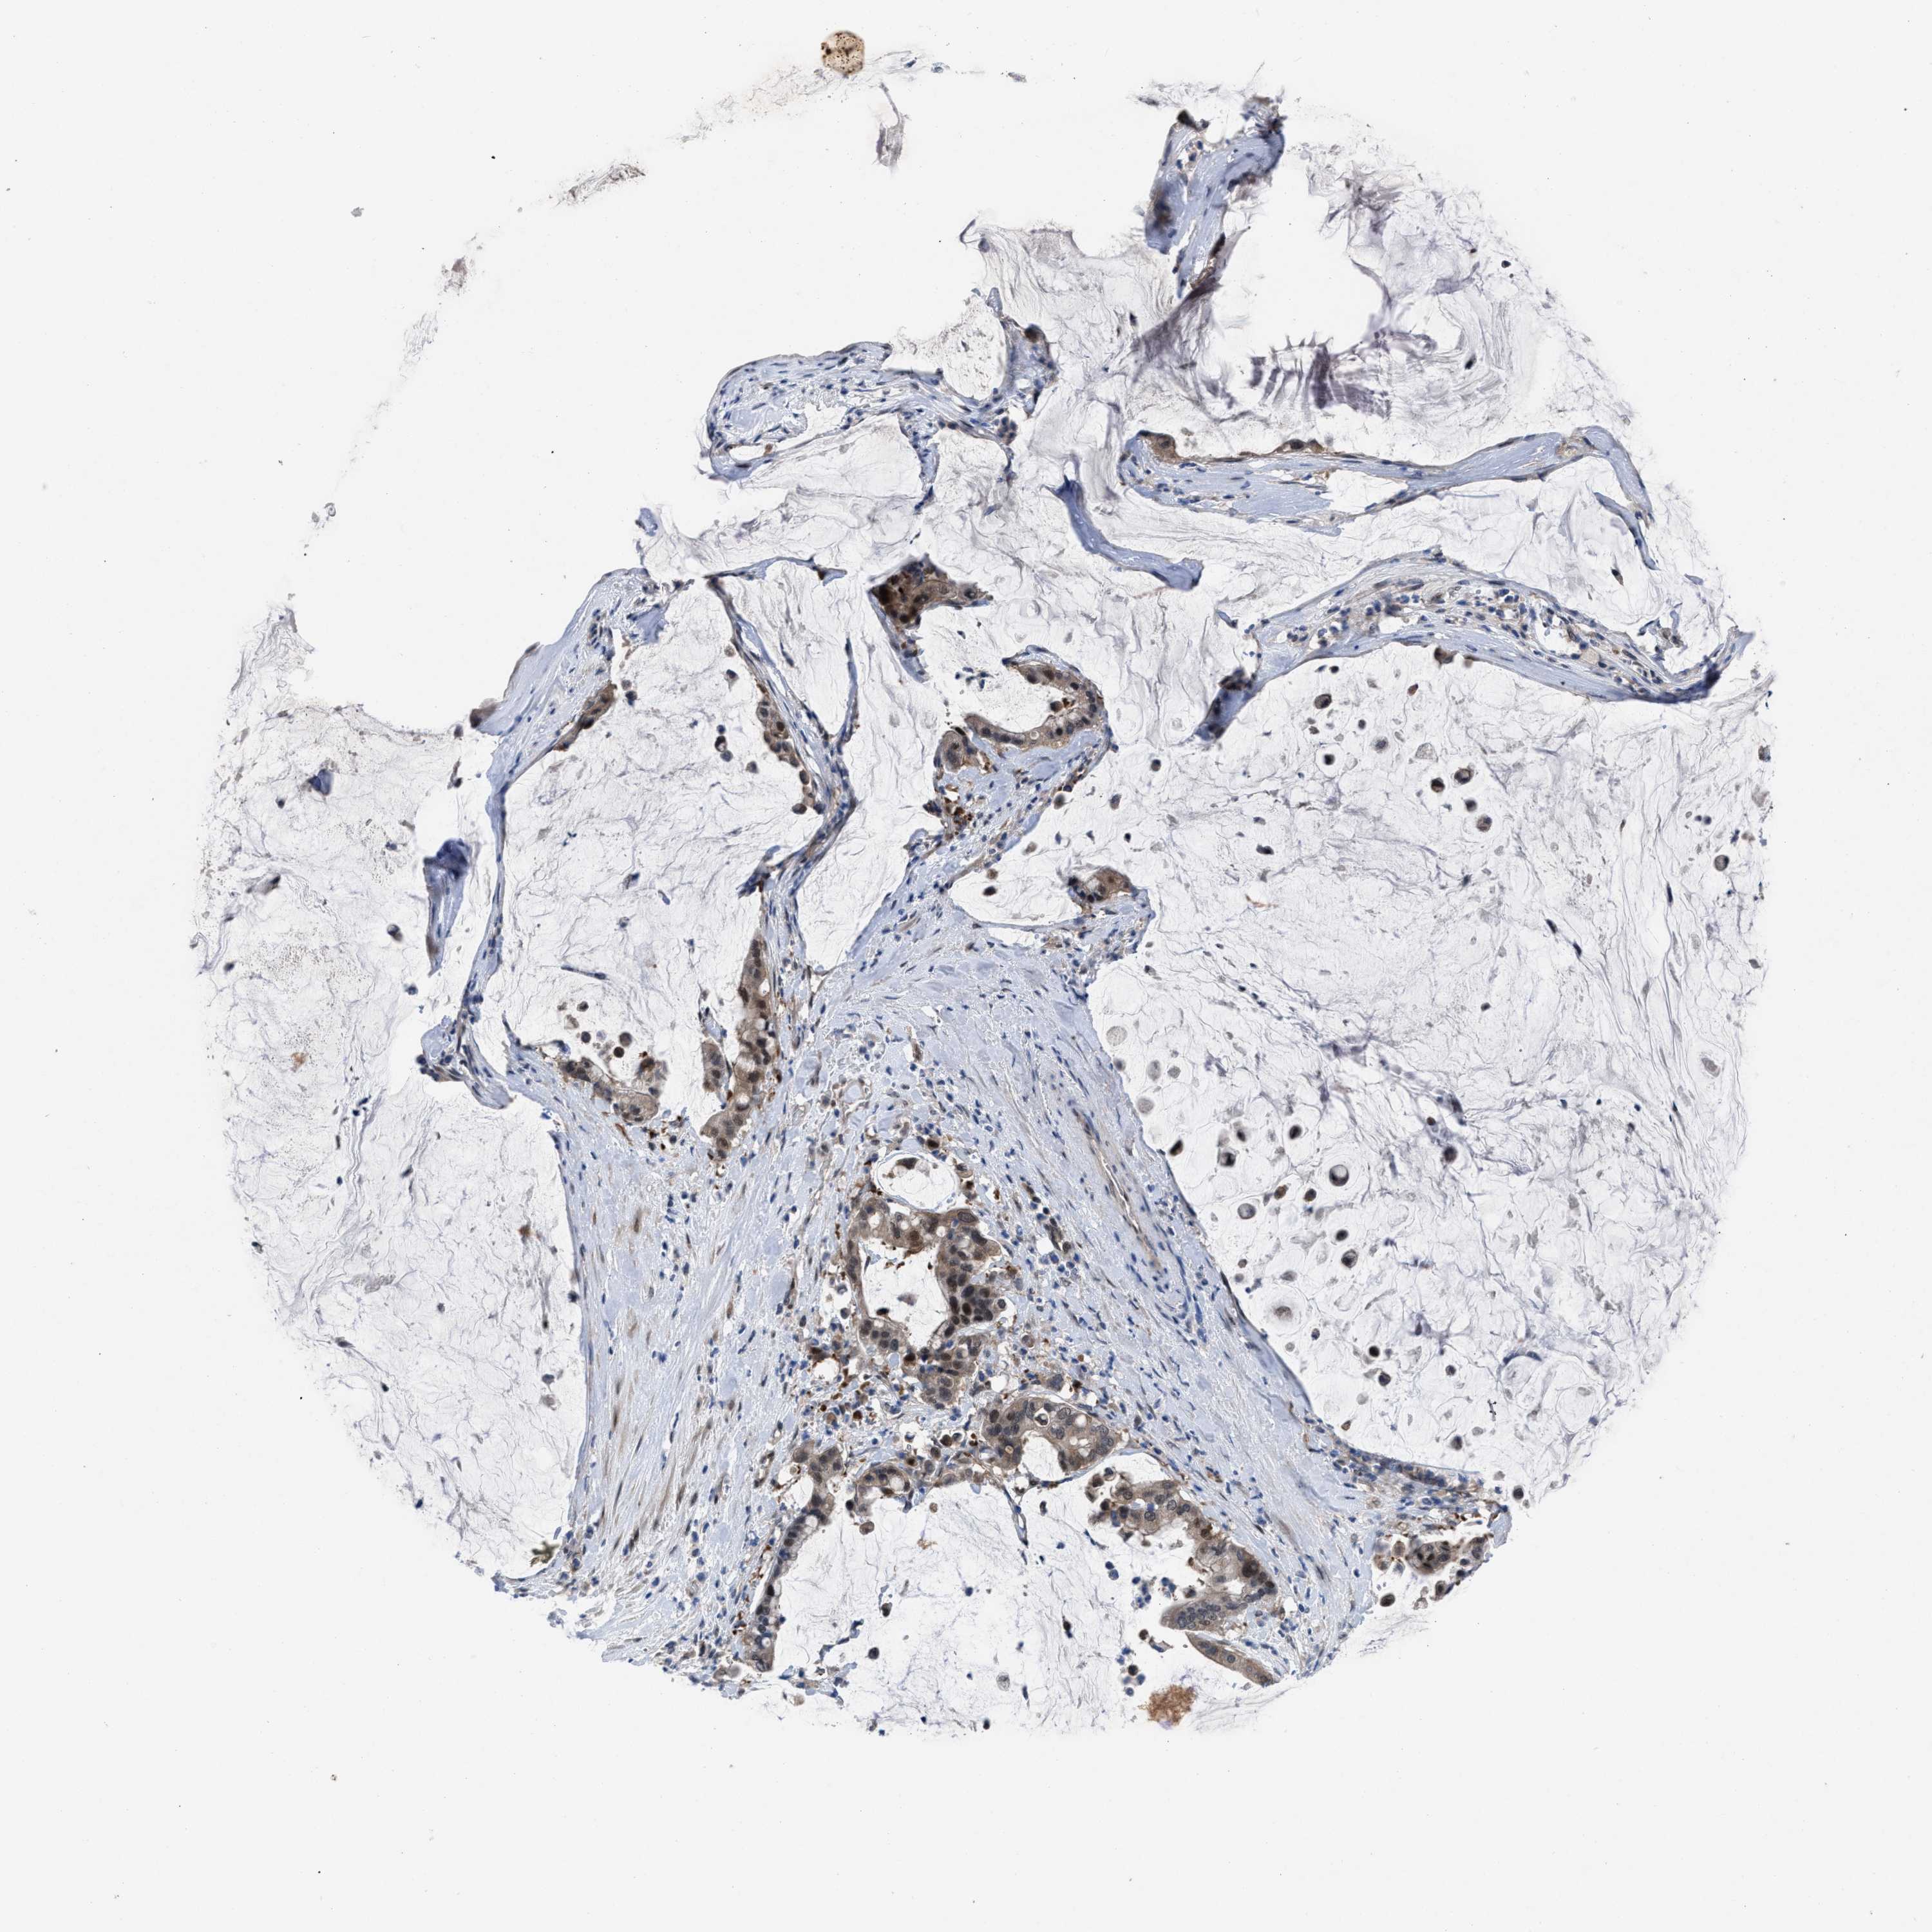

PANCREATIC CANCER - Protein expressioni

A mouse-over function shows sample information and annotation data. Click on an image to view it in a full screen mode. Samples can be filtered based on level of antibody staining by selecting one or several of the following categories: high, medium, low and not detected. The assay and annotation is described here.

Note that samples used for immunohistochemistry by the Human Protein Atlas do not correspond to samples in the TCGA dataset.

Antibody stainingi

Antibody staining in the annotated cell types in the current human tissue is reported as not detected, low, medium, or high, based on conventional immunohistochemistry profiling in selected tissues. This score is based on the combination of the staining intensity and fraction of stained cells.

Each image is clickable and will lead to virtual microscopy that enables deeper exploration of all samples and also displays staining intensity scores, fraction scores and subcellular localization as well as patient and tissue information for each sample.

Antibody HPA019011

Staining

High

Medium

Low

Not detected

Intensity

Strong

Moderate

Weak

Negative

Quantity

>75%

75%-25%

<25%

None

Location

Nuclear

Cytoplasmic/membranous

Cytoplasmic/membranous,nuclear

Adenocarcinoma, NOS